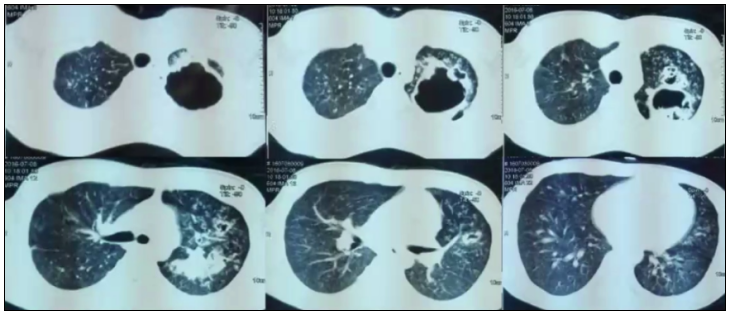

病例7:男性患者,21岁,反复咳嗽、咳痰、发热2年。胸部CT可见双肺散在结节状阴影,既往曾诊断结核,但在左上肺有一巨大的厚壁空洞,内壁不光整(图16),该患者是马尔尼菲篮状菌和曲霉的混合感染。

图片

图16  TSM患者肺部影像学表现

从上述病例的影像学可以看到,TSM的影像学表现多种多样,包括大片实变、结节、磨玻璃改变、粟粒样病变、肺门或纵隔淋巴结肿大、胸腔积液、空洞、坏死,以及细菌性肺脓肿,内壁光滑,甚至有气液平面,这与我们既往所认识的真菌影像学特征有所不同。研究显示,大部分HIV阳性患者胸部影像学表现形式多样,45.6%表现为斑片状浸润影或局限性肺实变,较少形成空洞病灶(8.0%)。HIV阴性TSM患者胸部影像学表现与HIV阳性患者相似,主要表现为肺部浸润影伴或不伴间质性改变,亦常出现胸腔积液。